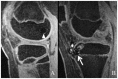

Context: As the intensity of youth participation in athletic activities continues to rise, the number of overuse injuries has also increased. A subset of overuse injuries involves the physis, which is extremely susceptible to injury. This paper aims to review the utility of the various imaging modalities in the diagnosis and management of physeal injuries in the skeletally immature population.

Results: Three major imaging modalities (radiographs, computed tomography, and magnetic resonance imaging) complement each other in the evaluation of pediatric patients with overuse injuries. However, magnetic resonance imaging is the only modality that offers direct visualization of the physis, and it also offers the best soft tissue contrast for evaluating the other periarticular structures for concomitant injury.

Conclusion: Imaging has an important role in the diagnosis of physeal injuries, and the information it provides has a tremendous impact on the subsequent management of these patients.